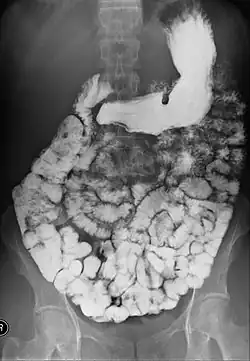

X-ray images are then taken in a supine position at intervals of 20–30 minutes. Real-time fluoroscopy is used to assess bowel motility. The radiologist may press or palpate the abdomen during images to separate intestinal loops. The total time necessary for the test depends on the speed of bowel motility or transit time and may vary between 1 and 3 hours.[17]

- Barium follow-through examinations are the most commonly used imaging technique in assessing patients with Crohn's disease, although CT and magnetic resonance imaging are widely accepted as being superior.[1] However Barium examinations remain superior in the depiction of mucosal abnormalities.[24] The features of Crohn's disease are well described by barium follow-through examinations, appearing as a typical "cobblestone pattern", but no information is obtained regarding extraluminal disease.[28] Radiographic imaging in Crohn's disease provides clinicians with objective evaluations of small bowel regions that are not accessible to standard endoscopic techniques.[29] Because of its length and complex loops, the small intestine is the most difficult part of the gastrointestinal tract to evaluate. Most endoscopic techniques are limited to the examination of proximal or distal segments, hence Barium follow-through remains in most centres the test of choice for the investigation of abdominal pain, diarrhoea and in particular diseases manifesting mucosal abnormalities such as coeliac and Crohn's disease.[26]